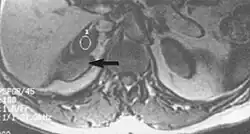

Fig. 3. Metal-related artifacts.[1]

Fig. 4. Metal-related artifacts.[1]

Metal artifacts occur at interfaces of tissues with different magnetic susceptibilities, which cause local magnetic fields to distort the external magnetic field. This distortion changes the precession frequency in the tissue leading to spatial mismapping of information. The degree of distortion depends on the type of metal (stainless steel having a greater distorting effect than titanium alloy), the type of interface (most striking effect at soft tissue-metal interfaces), pulse sequence and imaging parameters. Metal artifacts are caused by external ferromagnetics such as cobalt containing make-up, internal ferromagnetics such as surgical clips, spinal hardware and other orthopaedic devices, and in some cases, metallic objects swallowed by people with pica.[3] Manifestation of these artifacts is variable, including total signal loss, peripheral high signal and image distortion (Figs 3 and 4).[1] Reduction of these artifacts can be attempted by orientating the long axis of an implant or device parallel to the long axis of the external magnetic field, possible with mobile extremity imaging and an open magnet. Further methods used are choosing the appropriate frequency encoding direction, since metal artifacts are most pronounced in this direction, using smaller voxel sizes, fast imaging sequences, increased readout bandwidth and avoiding gradient-echo imaging when metal is present. A technique called MARS (metal artifact reduction sequence) applies an additional gradient, along the slice select gradient at the time the frequency encoding gradient is applied.